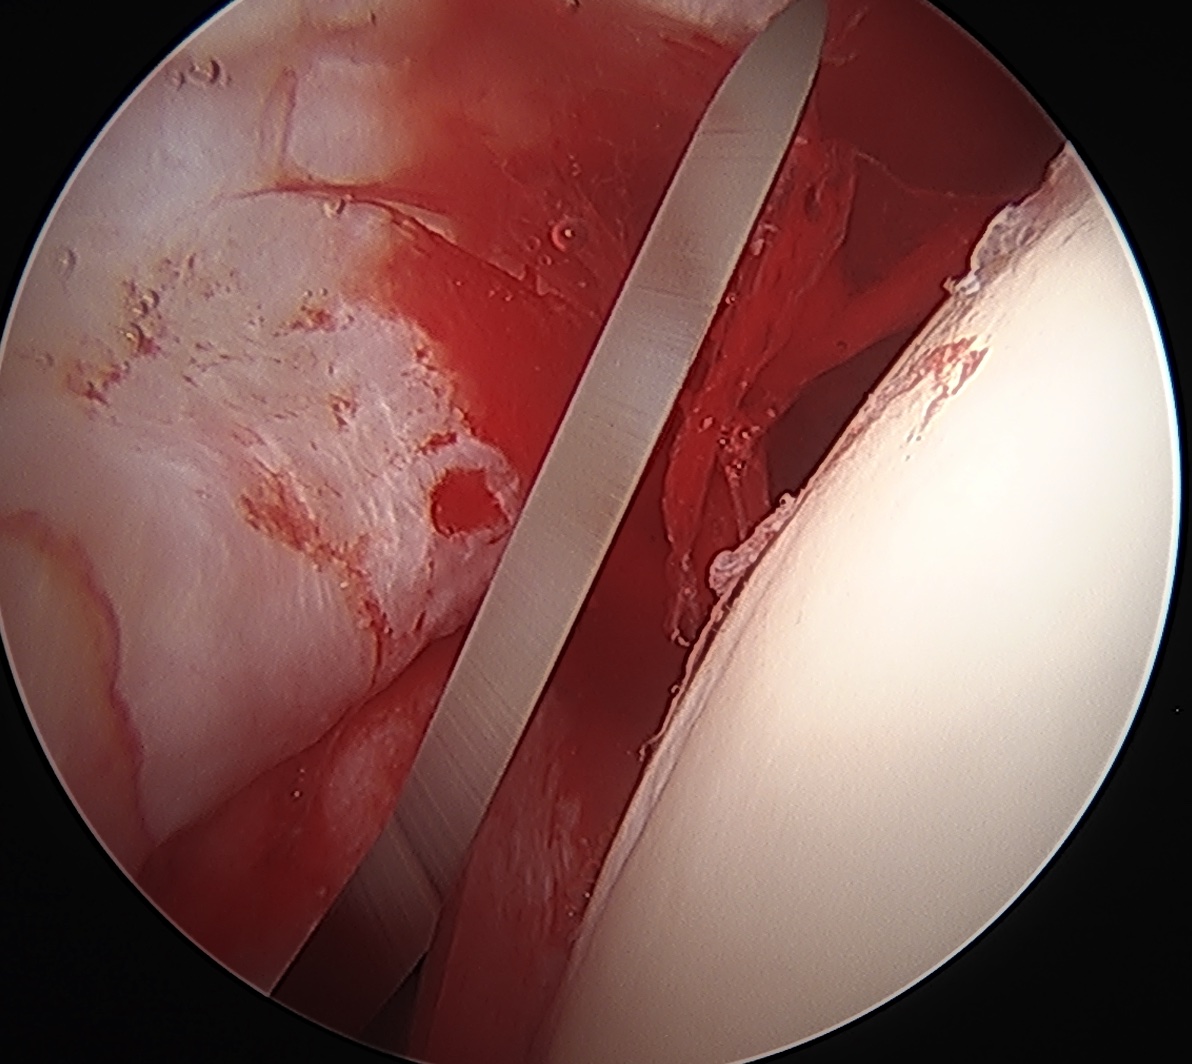

CAM resection

Capsule

- distal capsule suspension sutures / parachute technique

- T capsulotomy - better for large Cam lesions, needs repair

Placing distal capsule sutures to allow parachute technique / distal capsule suspension to expose Cam

T capsulotomy to expose large Cam at head neck junction